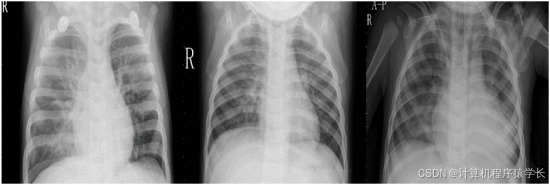

本文提出了一种轻量级深度学习模型,以准确筛查COVID-19肺炎的可能性。该模型基于14层卷积神经网络(CNN)和改进的空间金字塔池化模块(SPP),通过使用SPP的并行池层替换原始网络的最后几层来嵌入多尺度特征向量,实现的模型对各种输入尺度图像具有鲁棒性,能够适应各种大小的X射线图像,并捕获其中的图像特征。所构建的模型结构具有对多尺度输入图像进行特征提取的能力,使其能够识别各种严重程度的COVID-19疾病。根据实验结果,所提出的SPP-COVID-Net得到了0.946的精度,最后本文将该模型应用到系统页面,做了一个可用于分类不同类型肺炎的轻量级检测网站,医生可以立即运行,以便自动执行筛查过程。